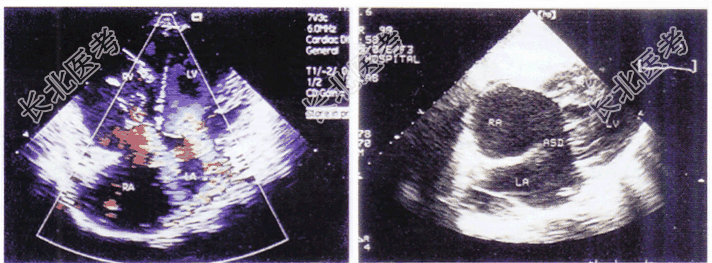

- 单项选择题如图,二维和彩色多普勒超声心动图所示, 该病例可诊断为

A、心内膜垫缺损部分型

B、心内膜垫缺损完全型

C、Ⅱ型房间隔缺损

D、二尖瓣、三尖瓣关闭不全

E、上腔型房间隔缺损